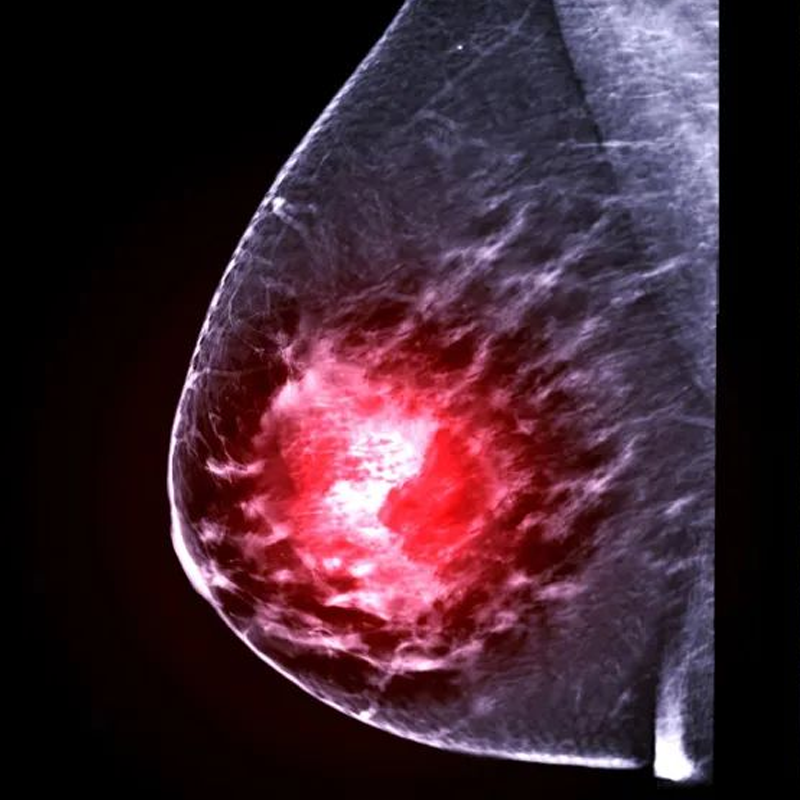

كتل غير طبيعية

- العقدة اللمفاوية

- عقدة الغدة الدرقية

- عقدة الصدر

عقدة الصدر